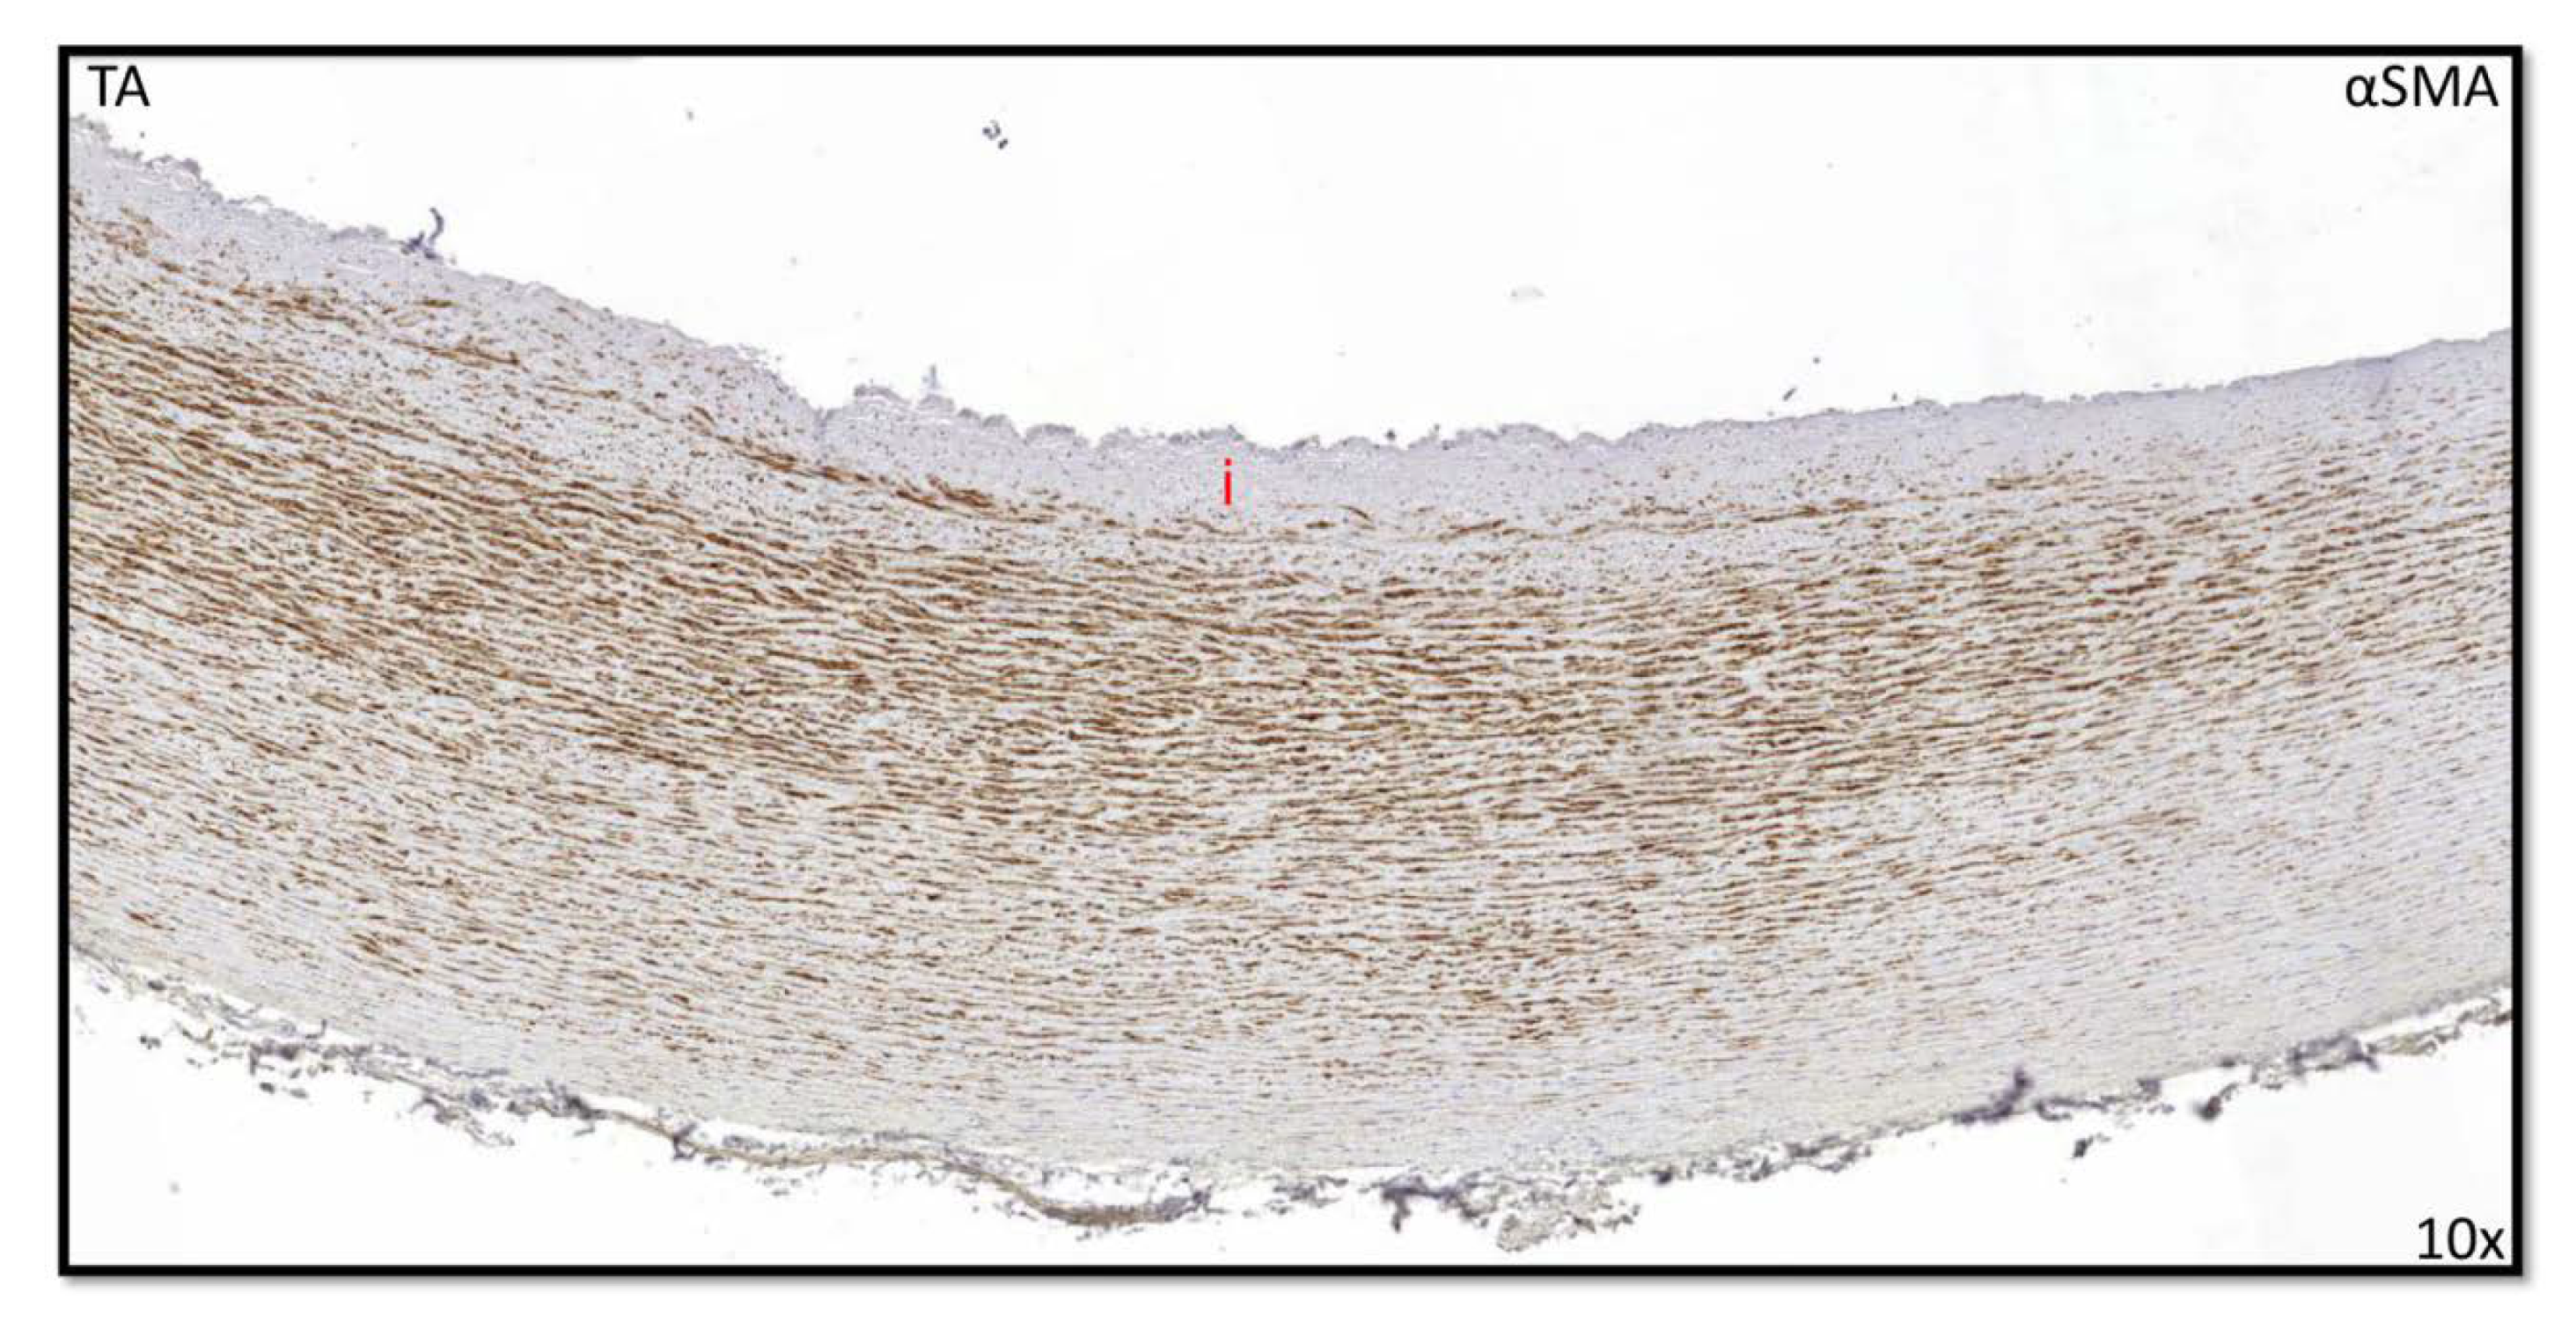

3.1. Development of the Innermost Layer of the Ascending Aorta

3.2. Development of the Middle Layer of the Ascending Aorta